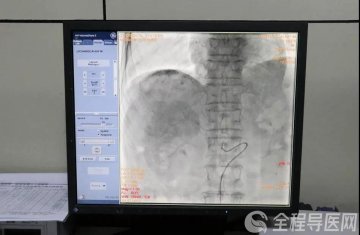

不仅如此,治疗前后的CT结果对比分析,肝转移瘤已明显变小,达到了几乎看不到的程度,肿瘤标记物指标回归正常,这些都说明肿瘤细胞正在被免疫细胞一点点消灭。